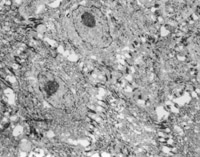

ԭλÇÐÈ¡´´Ãæ×éÖ¯²¡ÀíÇÐÆ¬²é³­£¬¼û»µËÀÉÏÆ¤×éÖ¯¼äÓдóÁ¿¿ÅÁ£Ñù×éÖ¯£¬ÐÂÉúÉÏÆ¤Ï¸°ûºÍ½ºÔ­ÏËά×éÖ¯³ÊÍÅÑùÔöÉú£¬²¢¿É¼ûµ½µäÐ͵ÄÀàËÆÓÚÌ¥¶ùƤ·ô½á¹¹µÄƤ·ôÅßÌ¥»ù(embryonic base,EB)(ͼ5-3-4a,5-3-4b)¡£MEBTÒ½ÖÎ10Ììºó£¬ÔÚ´´Ãæ±ßԵȡÉÏÆ¤×éÖ¯²¡ÀíÇÐÆ¬¿É¼ûµ½½ÏԭʼµÄÉÏÆ¤×éÖ¯¡£

5-3-4a ÐÂÉúÉÏÆ¤×éÖ¯ºÍ½ºÔ­ÏËάÔöÉú£¬¿É¼ûµäÐÍEB£¨Æ¤·ôÅßÌ¥»ù£© HE¡Á40

5-3-4b ÐÂÉúÉÏÆ¤×éÖ¯Öпɼû΢Ѫ¹Ü£¬½ºÔ­ÏËάºÍÉÏÆ¤Ï¸°û(¸Éϸ°û)ÐÎ³ÉµÄÆ¤·ôÅßÌ¥»ù×éÖ¯  HE¡Á40